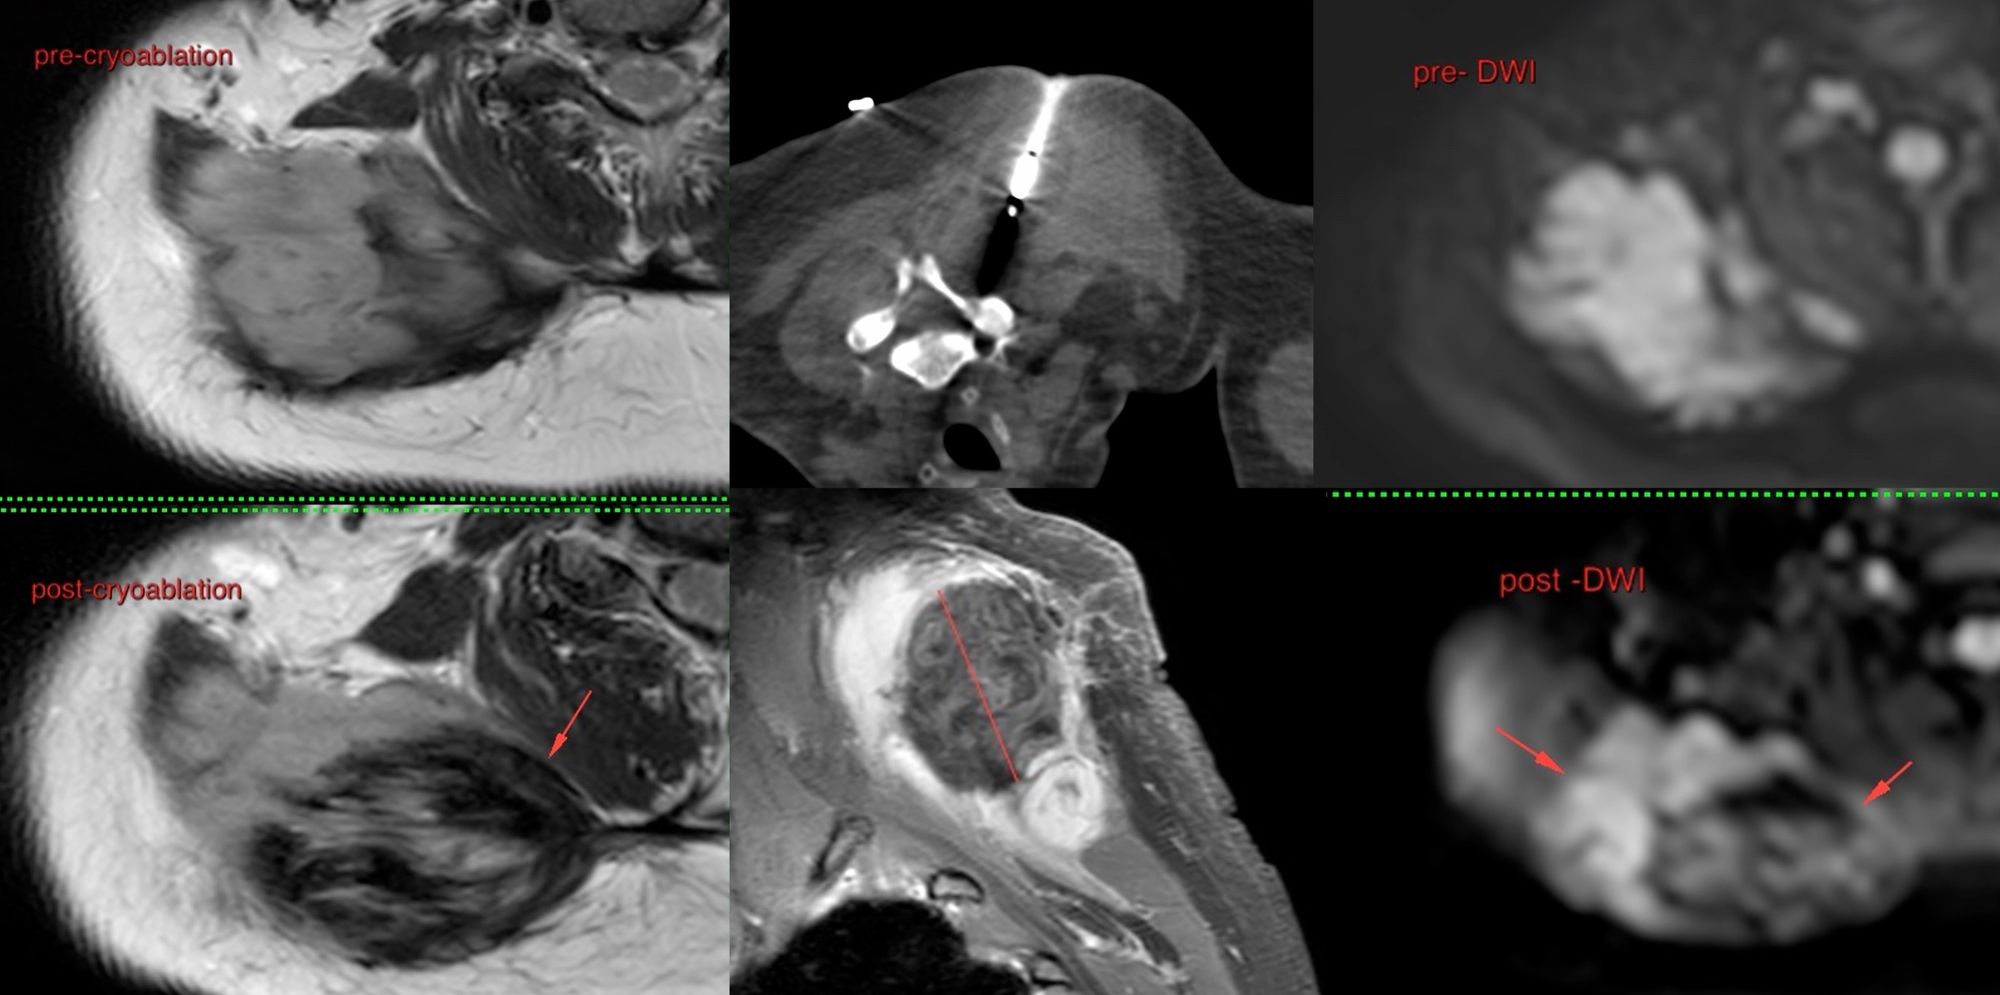

Case 53: Cryoablation of Extra-Abdominal Thoracic Wall Fibromatosis

Bhavin Jankharia - 06 August 2021